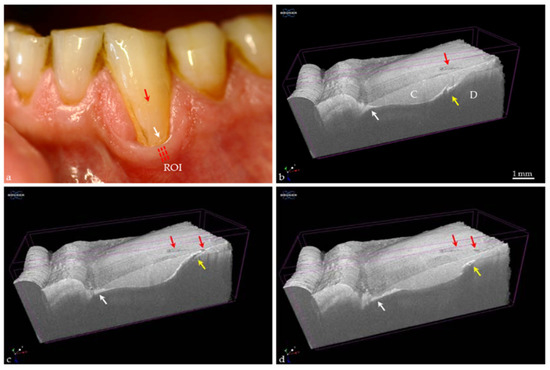

Figure 12. Canine tooth in vivo. (a) A cervical composite restoration (C) shows a margin discoloration (white arrow); (b,c) In the 3D and 2D OCT images, a margin gap with ingress of material is detected (red arrows). At dentin (D), an extensive interfacial gap has formed (white arrows); (d) Using quantitative light-induced fluorescence the image showed red fluorescence (red arrow) at the cervical restoration margin indicating bacterial activity by porphyrin invasion into the gap. There are no signs of “secondary caries” at the restoration margin, but the stability of the situation requires observation over time (monitoring).

Another highly relevant scenario in need of diagnostic information is the field of restoration assessment. In Figure 12, a clinical case of a discolored restoration margin gap is shown. However, it could be seen that discoloration at margins of composite restorations is not an indicator for deeper interfacial gap formations. OCT allows the identification of weak spots in the composite restorations and the differentiation of the findings associated with discolorations. If a carious lesion is detected, the treatment depends on its longitudinal stability. If progression is identified, treatment will be related to the extent of the lesion and speed of progression (activity).

Today, there is no single method that can be considered the gold standard for imaging the morphology of the hard tooth tissue while simultaneously assessing the longitudinal activity of a carious lesion. Quantitative light-induced fluorescence (QLF) is known as an imaging technique with the option to visualize present bacterial activity in carious lesions [11,47]. The method is based on autofluorescence of tooth hard tissues and quantifies the autofluorescence difference between sound and carious (pathogenic) enamel. This difference results from the decrease of autofluorescence with increasing porosity of progressing subsurface enamel lesions [48]. With the QLF-D Biluminator™ 2 (Inspektor Research Systems bv, Amsterdam, The Netherlands), a tool becomes available that makes it possible to additionally image and quantify the red fluorescence of oral bacteria induced by various porphyrin species as products of anaerobic bacterial metabolism. Thus, detection of low porphyrin concentrations would be an indicator of early stage caries formation [49]. Now, OCT, contrary to histopathological assessment, can provide submicrometer resolved tomographic images of tissues in vivo. We hypothesized that the combination of both imaging techniques would be beneficial as the three-dimensional lesion morphology could be brought together with the microbial and metabolic findings in real-time, as well as of one and the same tooth area. Such an approach should hopefully facilitate more accurate treatment decisions and the assessment of the restoration outcome during follow-ups.